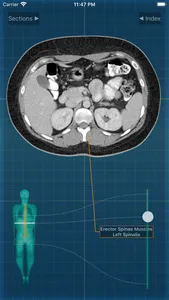

X-Anatomy is a transaxial cross-sectional human anatomy interactive medical imaging atlas using CT images, designed for medical professionals & all students of anatomy.

* Includes hundreds of images from actual human patient body scans.

* Use the intuitive BODY LOCALIZER to show you where you are as you scroll through the body, as well as the general region of the anatomic structure

INCLUDED body section modules cover the major body sections from head to pelvis: CT Brain, CT Neck, CT Sinuses, CT Chest, CT Lungs, CT Abdomen & Male Pelvis, CT Abdomen & Female Pelvis.